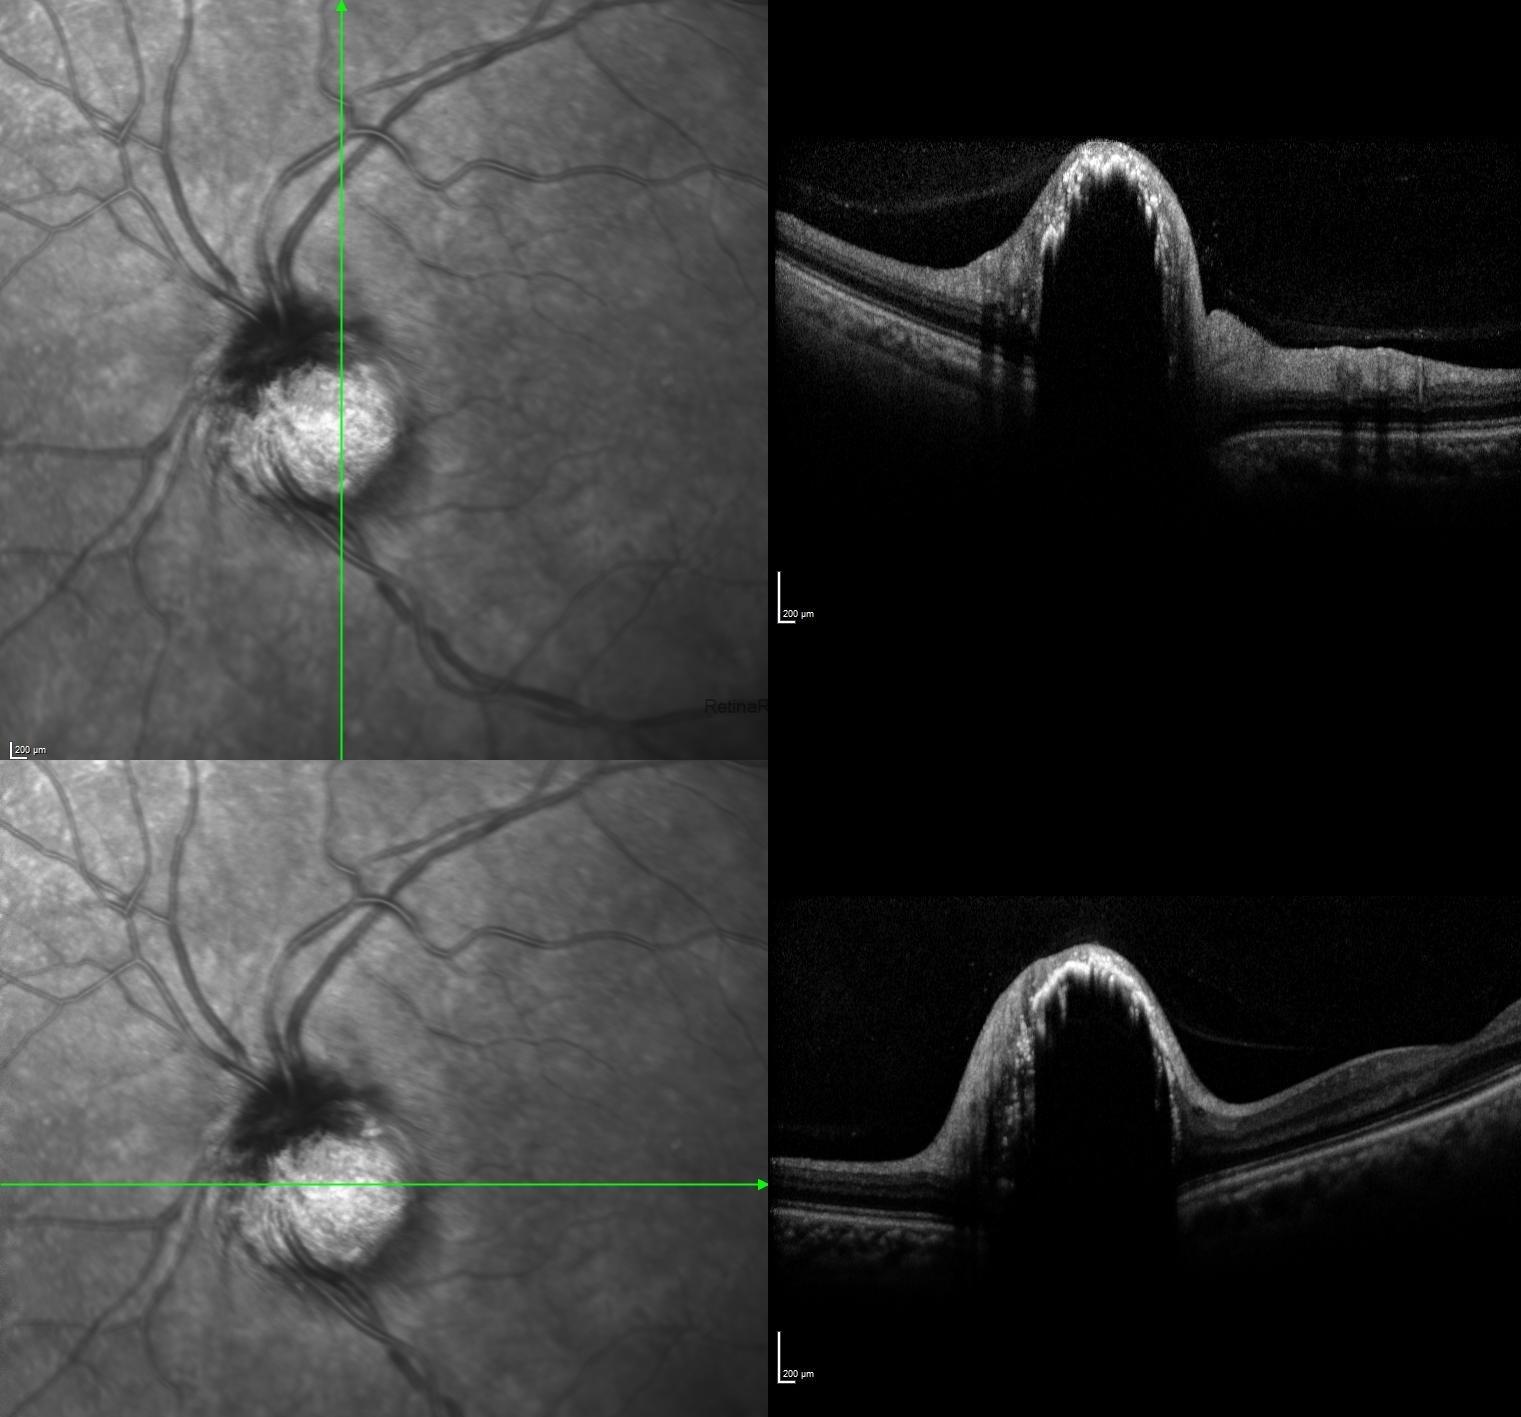

Optical coherence tomography scans passing through the lesion exhibited nodular elevated lesion with areas of irregular hyperreflectivity overlaying the tumor in additon to dense posterior shadowing effect.